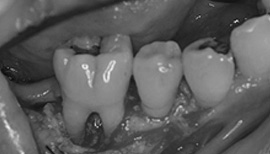

術中

歯周外科処置をおこない、トンネリングをおこないました。

治療後

根の間に歯間ブラシが通るようになりました。しかしこの処置をするには、根の間が虫歯になりやすいので、しっかりブラッシングでき、メインテナンスに来院できる方が適応症です。